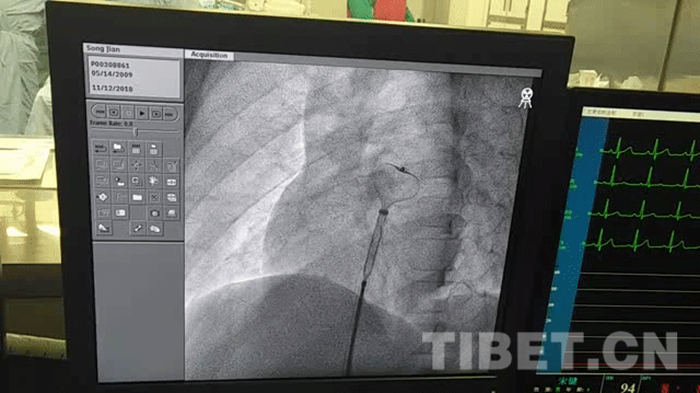

圖為(wei) 宋鍵進行心髒介入手術時,放入封堵傘(san) 。 攝影:孫健

12日上午9點30分左右,在醫護人員的鼓勵和陪同下,宋鍵前往手術室接受心髒介入手術。剛躺在手術台上時,因為(wei) 緊張和恐懼,宋鍵忍不住發抖,醫護人員為(wei) 了轉移他的注意力,拿出手機讓他看動畫片,並不斷安撫他。

注入麻醉劑後,宋鍵慢慢恢複平靜,放鬆下來。手術開始後,醫生和護理人員聽到宋鍵口中不斷傳(chuan) 來“哼”聲,以為(wei) 他在哭泣,詢問後才得知,原來小宋鍵在“哼曲兒(er) ”,這讓手術室的醫護人員忍不住欣慰大笑。伴隨著宋鍵的曲聲,整台手術順利完成。